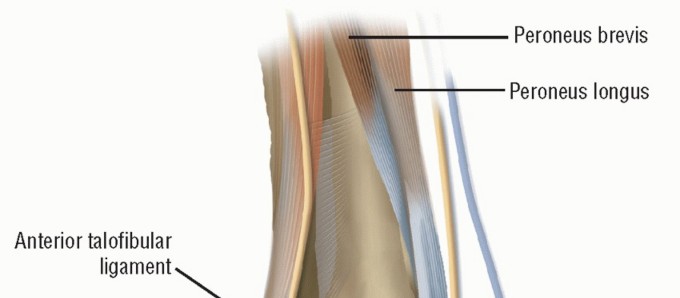

DEFINITION Lateral ankle injuries are among the most common musculoskeletal injuries in the athletic populati…

DEFINITION Lateral ligament instability occurs in some patients after an inversion injury. 38 Although an inv…